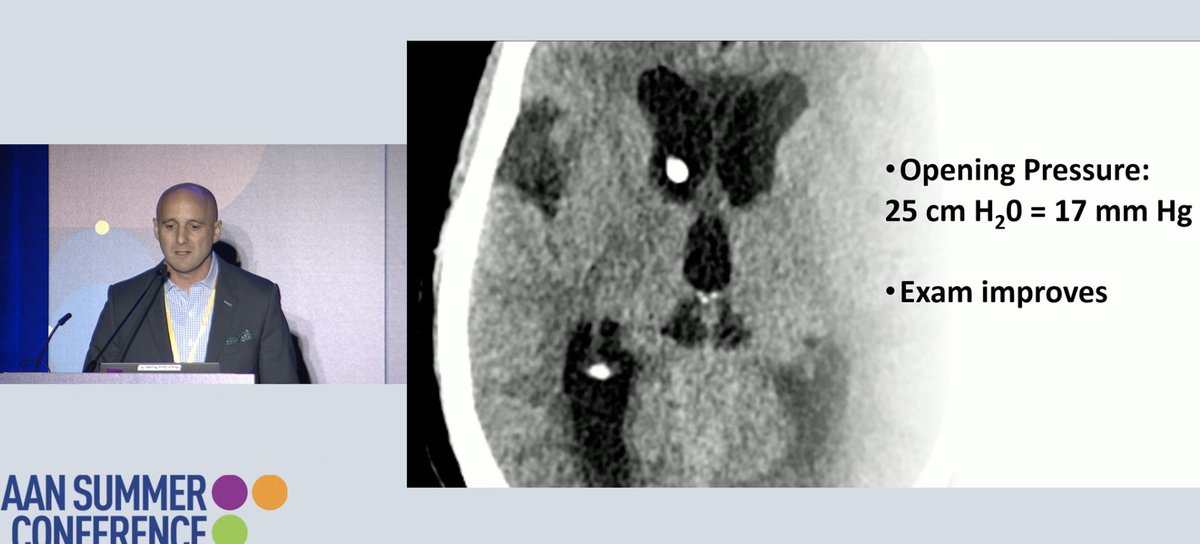

This is not GBM.... what is it, #NeuroTwitter?? the key -- pull your eyes away from the most exciting part of the brain (in this case the left) and look at the whole picture. From #JoshKlein's lecture @ #AANSC @aanmember